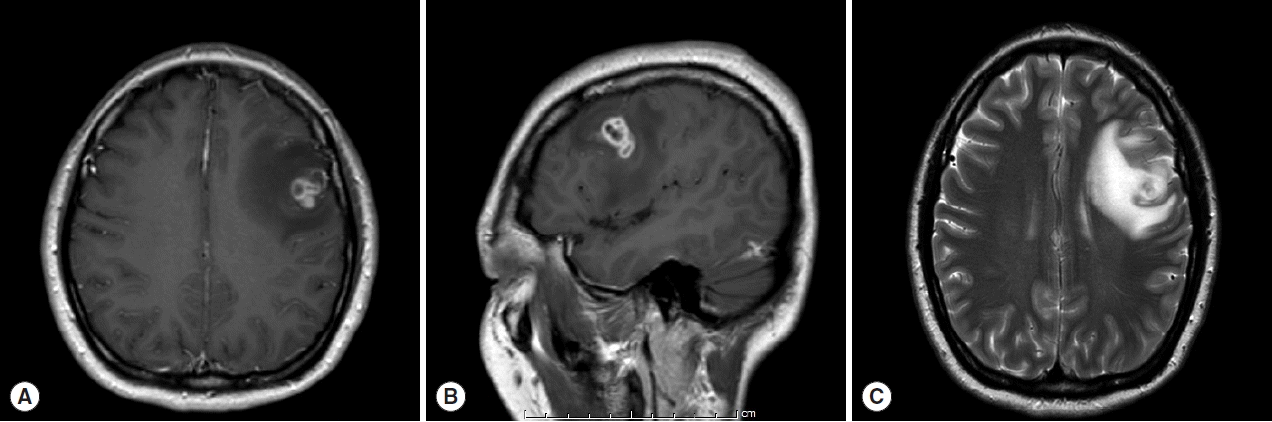

A 30-year old Thai female presented to the outpatient clinic with generalized tonic-clonic seizure 1 week ago. The duration of the seizure was less than 1 min. The patient passed out for 1 hr, and gained consciousness without memory deficit. There was no history of fever, vomiting, headache, or visual disturbances. No history of previous accident, drug allergy, or cancer was present. Her physical examination was normal. The brain MRI revealed a conglomeration of several small ring enhancing lesions of 1.9×1.4×1.6 cm in size, at the cortical posterior left middle frontal gyrus. Neither midline shift nor hydrocephalus was seen (Fig. 1). A chest x-ray showed an unremarkable finding. No abnormal calcification was detected by plain radiograph of the femur. Routine blood examinations showed an absence of eosinophilia, and stool examinations showed no parasites.

Regarding the imaging studies, Kim et al. [5] described the features of sparganosis by MRI as widespread white matter degeneration and cortical atrophy, and mixed-signal lesions with irregular dense enhancement of central foci. Viable cysticerci can be diagnosed on MRI as cystic lesions which appear hypointense on T1 and hyperintense on T2 with an eccentric nodule. When the cyst degenerates, fluid leaks out and creates inflammation which is seen as peripheral enhancement on MRI and CT. Also, variable degrees of edema may be seen in the surrounding tissues [6,7].